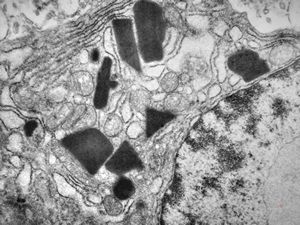

M,58y. | crystalline inclusions in hepatocyte after unknown medication

M,58y. | crystalline inclusions in hepatocyte after unknown medication